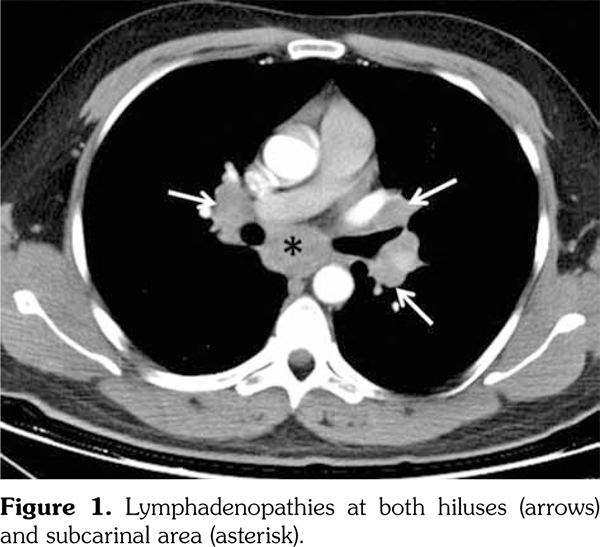

Lymph node biopsy was performed by broncoscopy and endobronchial ultrasonography. Biopsy result was compatible with granulomatous disease. All the infectious studies performed on pulmonary lymph node tissues were negative. Angiotensin converting enzyme level was at the upper limit with a value of 47.6 U/L (normal: 8-52 U/L). Sarcoidosis was found to be compatible with the condition after excluding tuberculosis. Etanercept was ceased following the diagnosis of sarcoidosis. No additional medical treatment was suggested for sarcoidosis. Non- steroid anti-inflammatory drugs were prescribed for the control of AS. Five months later, follow- up thorax computed tomography scan showed resolution of the mediastinal lymphadenopathies (Figure 2).

However, pain, dysfunction in daily living activities related with AS, high disease activity markers (erythrocyte sedimentation rate: 53 mm/hour, C-reactive protein: 40 mg/L [normal: 0-6 mg/L], and Bath Ankylosing Spondylitis Disease Activity Index of 6.3 [normal: 0-4]) during the period without etanercept prompted us to consider another anti-TNF-α agent. At the seventh month of etanercept cessation, golimumab with the dosage of 50 mg/month was commenced to compete with the symptoms and findings associated with AS. At the ninth month of follow-up period after inception of golimumab, the patient had no pain with normal disease activity markers. There were no pathological findings regarding sarcoidosis in the examination of the pulmonary system (Figure 3). A written informed consent was obtained from the patient.